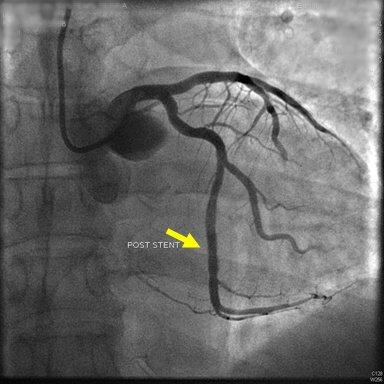

2.配合医生穿刺:一般采用Seldingers经皮穿刺法。病人取仰卧位,局麻后﹙儿童采用全身麻醉﹚在严格的无菌操作下自股静脉、上肢贵要静脉、锁骨下静脉$2右心导管术$3或股动脉、肱动脉$2左心导管术$3插入导管到达相应部位。整个检查均在X线透视下进行,并作连续的心电和压力监测。动脉穿刺成功后注入肝素3000U,随后操作每延长lh追加肝素1000U。